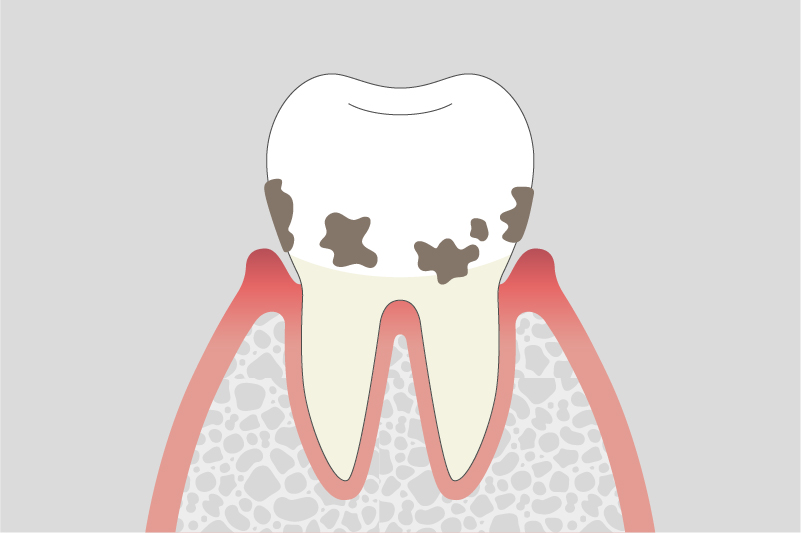

02.

軽度歯周病

歯周ポケットが深くなり、歯ぐきの腫れが続く。骨が少し溶け始めます。